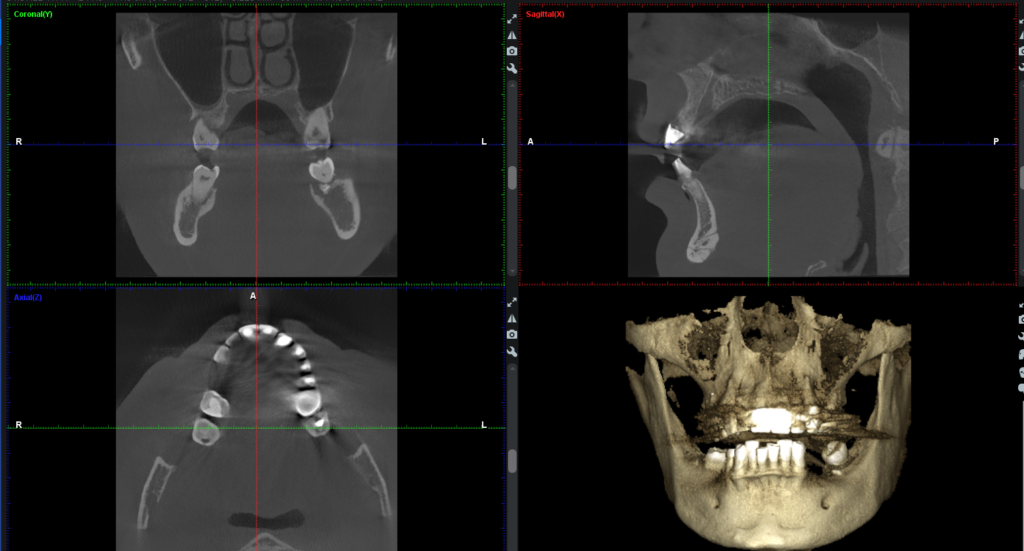

1. Първо се прави 3D рентгенова дигитална снимка, познато още като CBCT, което да покаже обема на костта около бъдещите импланти:

При самата обработка на изображенията д-р Парушева може да види с точност да микрон къде трябва да бъде поставен импланта и под какъв ъгъл. Не само това, но тя има възможността да види какво е състоянието на костта, къде се намира нервът на долната челюст, синусите, колко е дебела костта и да го позиционира така, че да бъде правилно поставен, без да се очакват допълнителни проблеми: